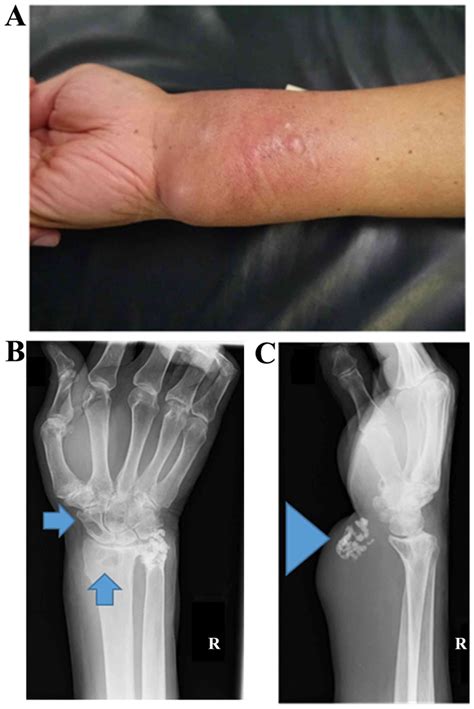

One of the primary challenges in diagnosing a sarcoma is that early-stage symptoms are often non-specific. Many patients first notice a lump that may or may not be painful. Because these lumps are often mistaken for benign cysts or sports injuries, they can go undiagnosed for months. It is important to pay attention to persistent symptoms that do not resolve over time.

• A painless or painful lump that is growing in size under the skin.

• Unexplained swelling or a feeling of "heaviness" in an arm or leg.

Once a doctor suspects a sarcoma, they will utilize a combination of diagnostic tools to confirm the diagnosis and determine the extent of the disease. The journey to a diagnosis usually involves imaging tests, such as X-rays, MRIs, or PET scans, which help identify the exact location and size of the tumor. A biopsy—where a small sample of the tissue is removed and examined under a microscope—is the gold standard for confirming exactly what is a sarcoma in a specific patient.